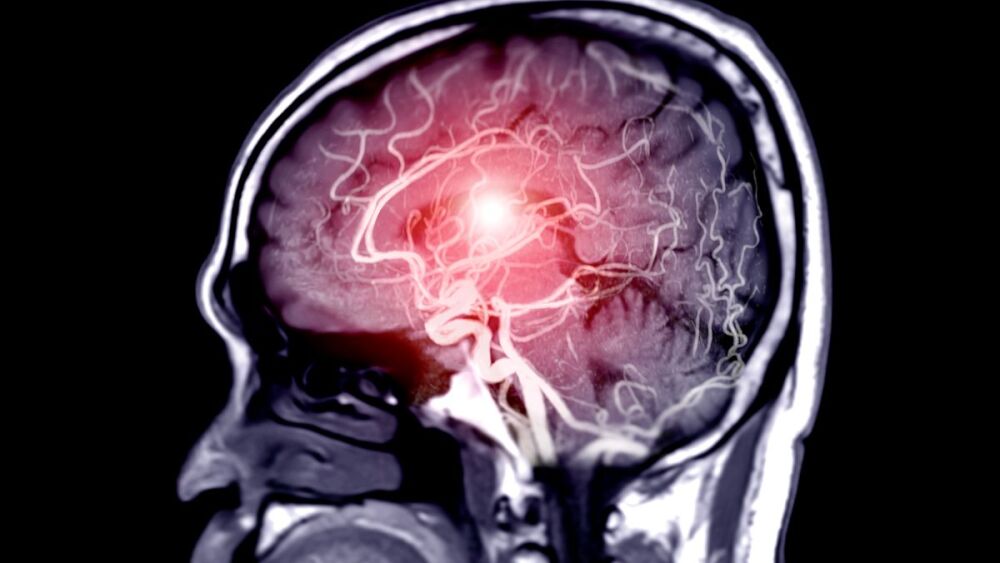

A study published in JAMA Neurology found stroke patients received higher levels of treatment at comprehensive stroke centers vs. the nearest stroke center

The results of the study, published in JAMA Neurology this week, found that stroke patients were more likely to receive endovascular therapy at comprehensive stroke centers in comparison to the nearest stroke center to the patient.